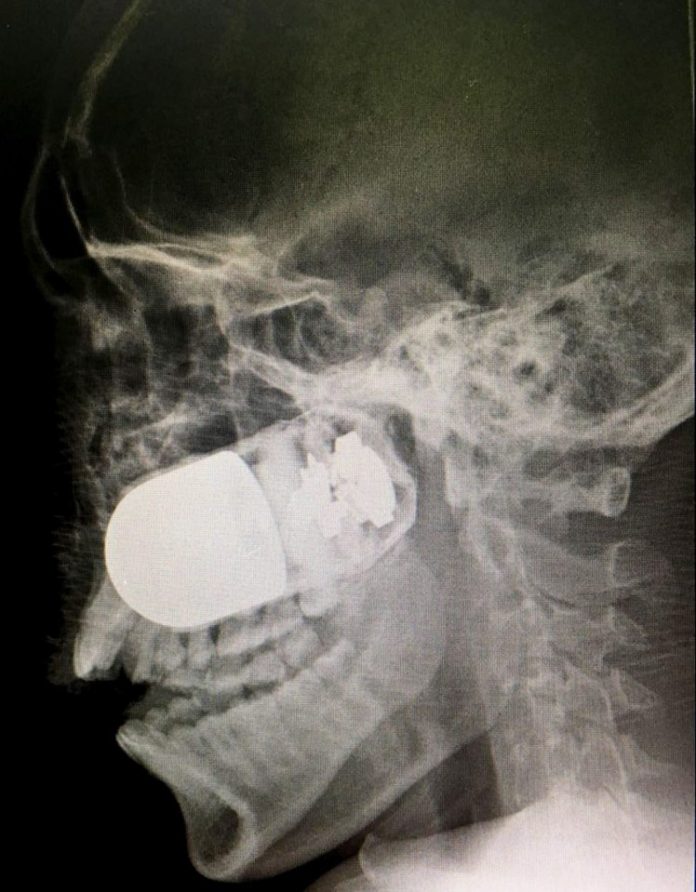

Yes, that is a live grenade lodged in the skull of a soldier.

The solider, Mr Arango, works for the eighth division of the Arauca Army and is now out of danger, although he is said to be recovering under strict medical observation.

How the grenade became lodged in his face is still under investigation.